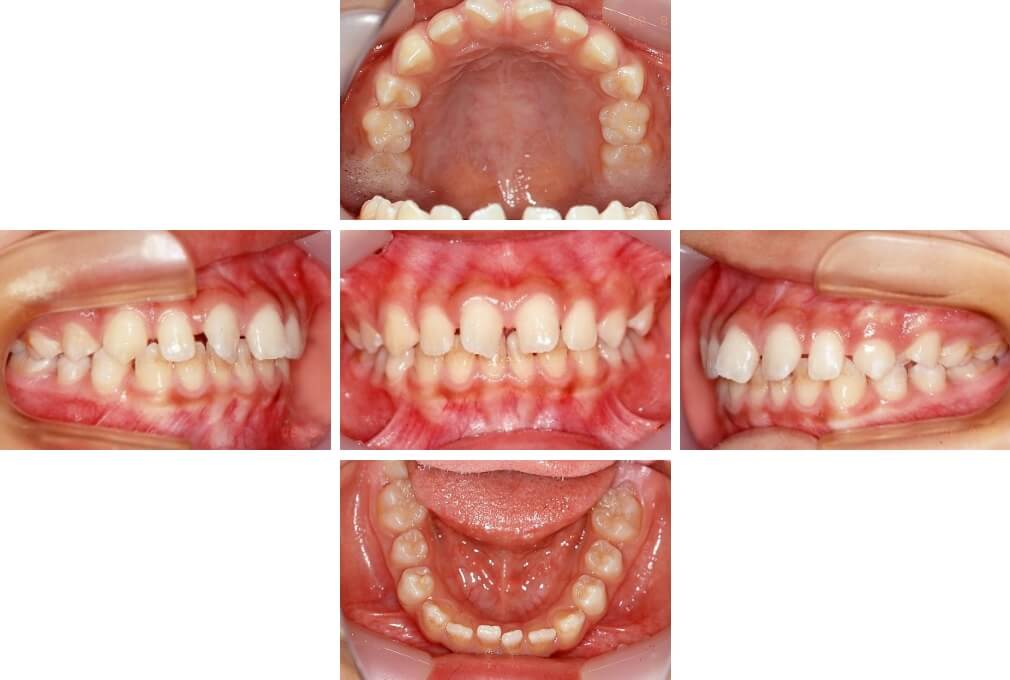

CASE:04

アングルⅢ級傾向を持つ叢生

初診時年齢 22歳

性別 女性

治療費の目安 105万円程度(治療開始時)

上顎右側犬歯が唇側に転位していることを主訴に県内歯科医院から紹介来院された。骨格的にはⅢ級傾向で上顎右側犬歯が唇側転位となり、側切歯が口蓋側に転位していた。下顎前歯が叢生になっていることも相まって上下の正中線は右側に大きくずれていた。アングルⅢ級傾向を持つ上下顎前歯部叢生と診断した。

上下顎小臼歯を抜歯していただき上顎舌側、下顎唇側マルチブラケット装置を使用して動的治療を行った。矯正用ゴムの使用など協力状態も良く、正中線の大きな移動があったのも関わらず2年10カ月で装置を撤去し保定へ移行した。保定移行後14年が経過し、ご息女の診察でご来院いただいていたことから、口腔内を拝見したが、下顎前歯のわずかなずれがあったものの大きな歯列の乱れはなく歯列は安定していた。動的治療期間2年10カ月間。

治療前

22歳6か月

治療後

動的治療期間2年10カ月間

25歳6か月

治療終了

動的治療終了後2年2カ月

28歳8か月

14年経過

動的治療終了後14年7カ月

40歳1か月